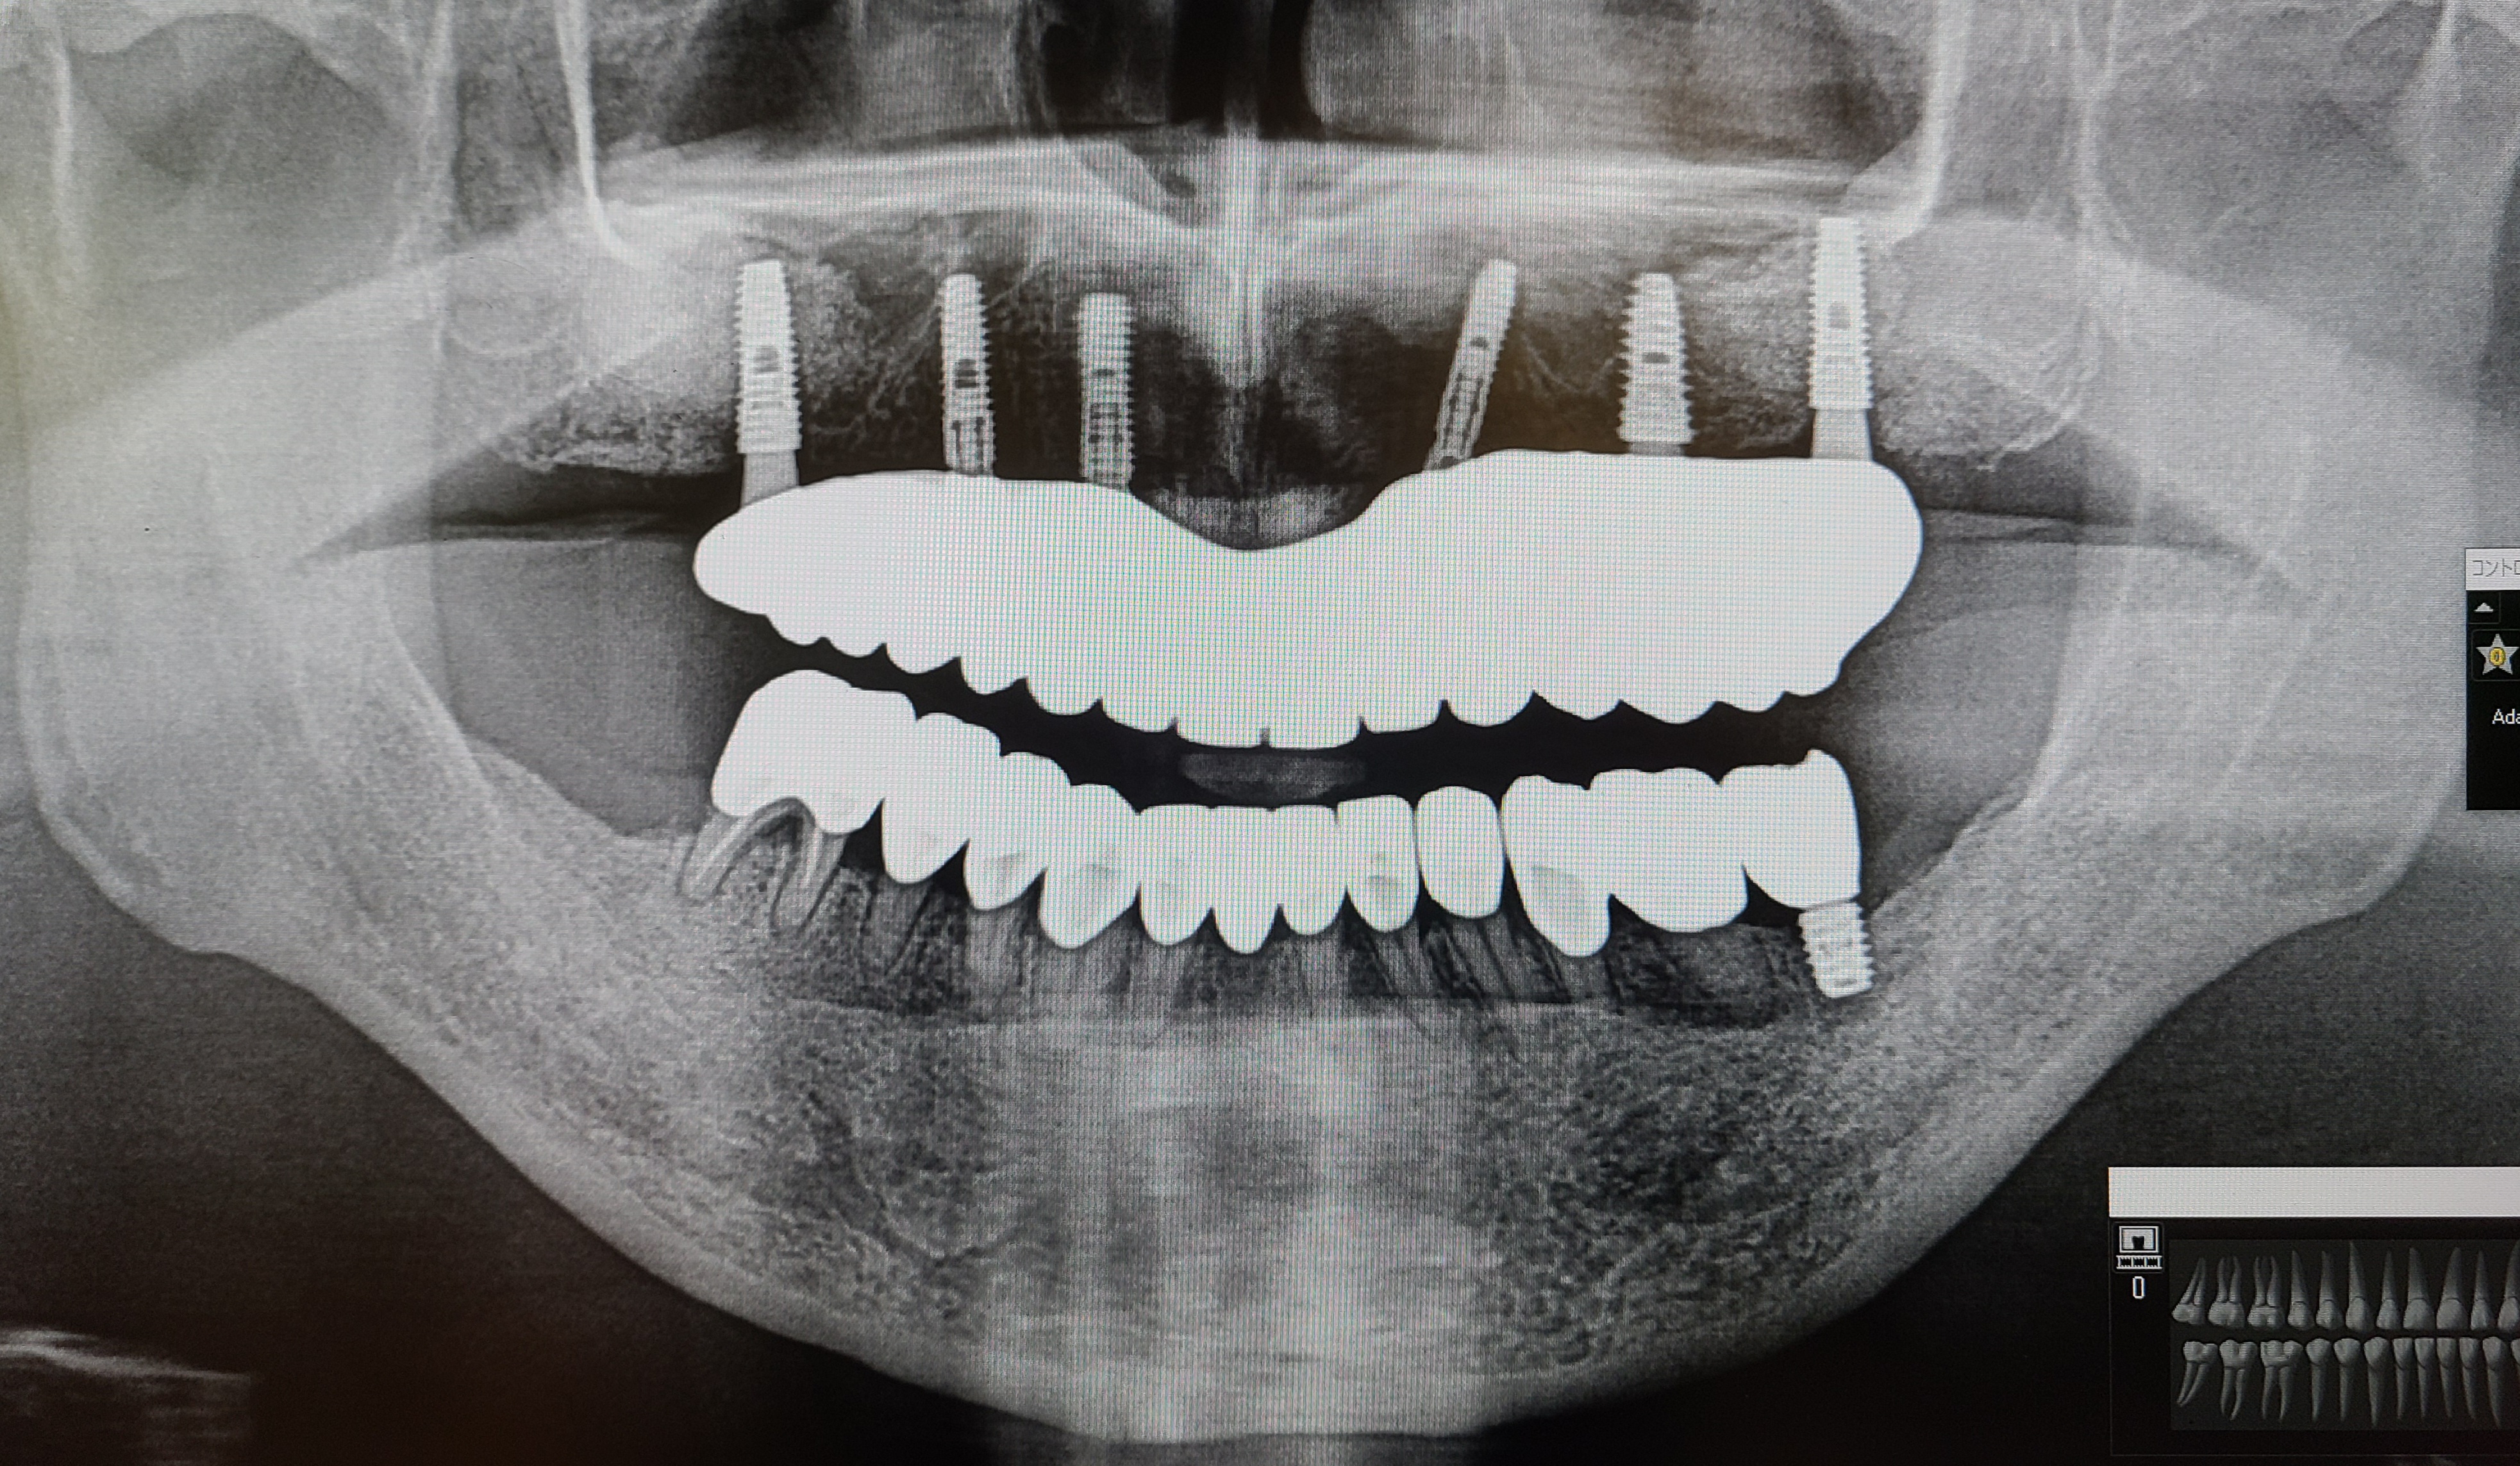

レントゲン・CT撮影をし残せる歯残せない歯の状態確認をし全体的な治療計画を立てます。

オールオンインプラント治療は上か下かでの選択ができます。残せる歯がある方ではジルコニアやセラミックを被せての治療が可能かの診断もします。

3.CT、ガイドをつくるための型どり

オールオンインプラントオペをするためにCTデータをもとにオペの設計をし、インプラントをいれる位置や直径、長さを決め患者様専用のガイドを作成します。

骨をつくるオペが必要かどうかでガイドを作成するタイミングが変わります。

元々歯がない状態の方や、抜歯が必要な歯があったとしても骨をつくるオペが必要でない方はすぐにガイドの作成に勧めますが、骨をつくるオペをした場合は最低6か月は待ってからCTで骨の状態を確認してガイドの作成に進みます。